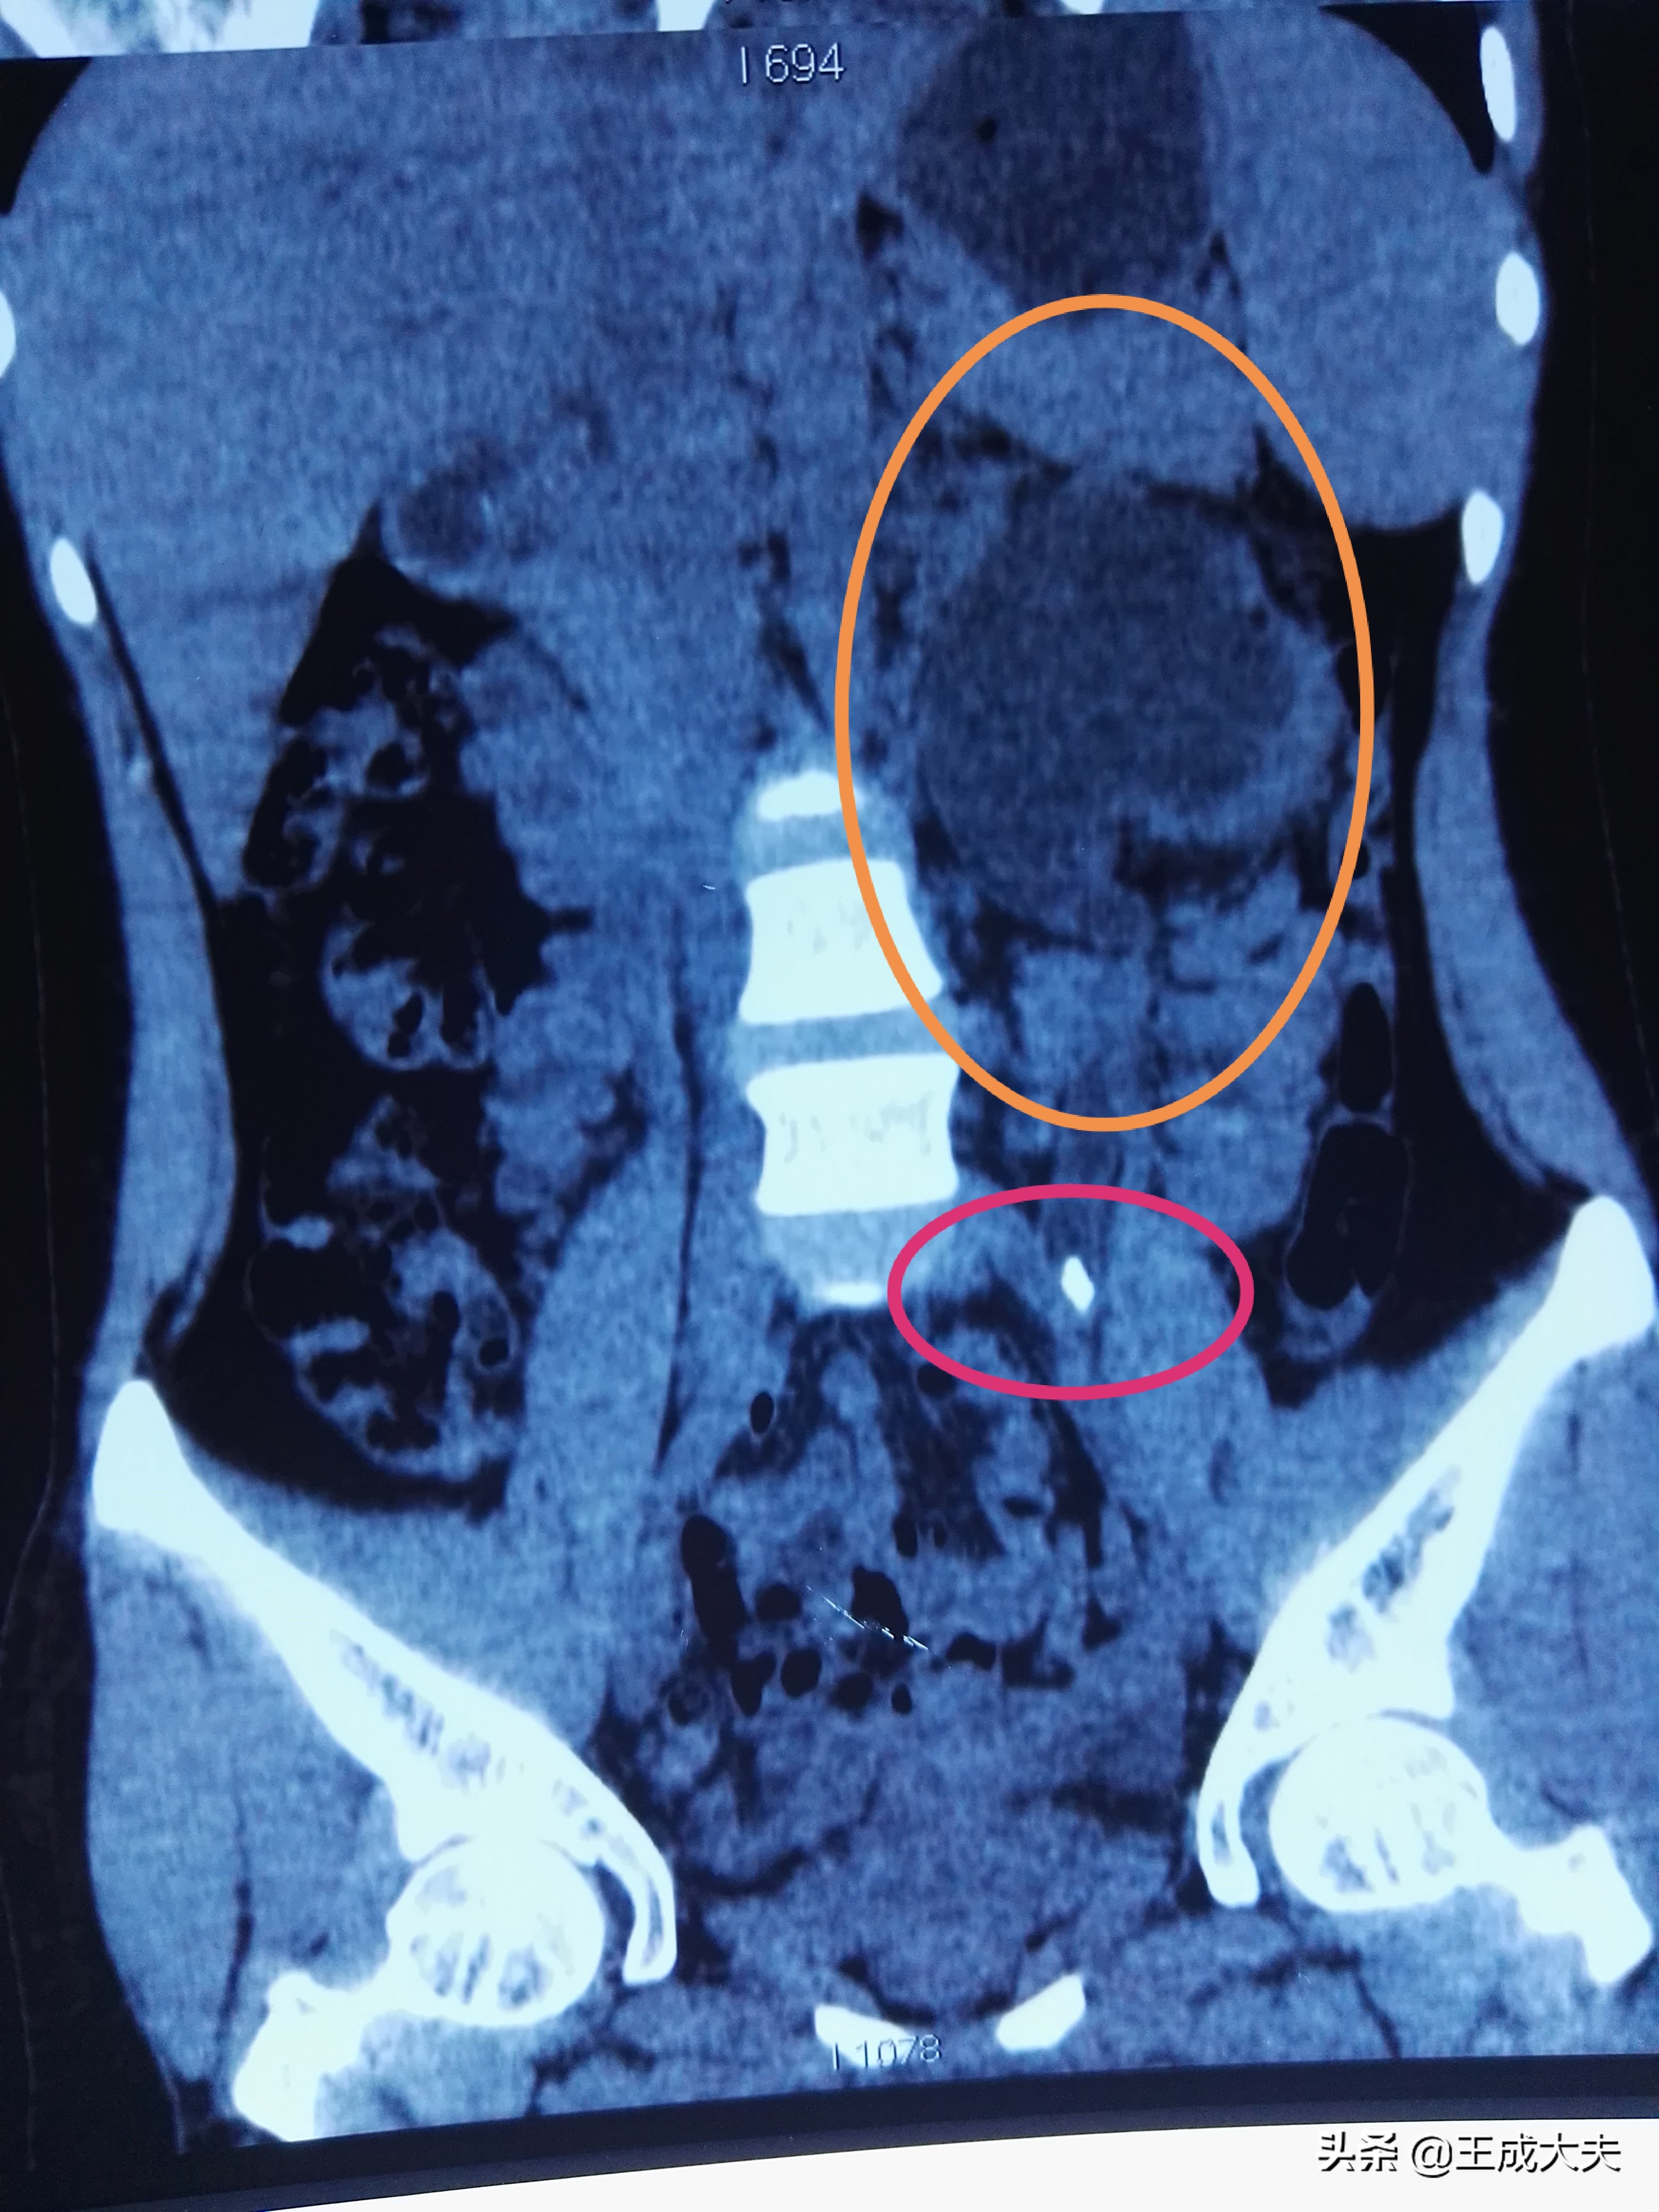

CT提示左输尿管结石(红圈内),左肾重度积水(黄圈内黑色部分,左肾功能受损